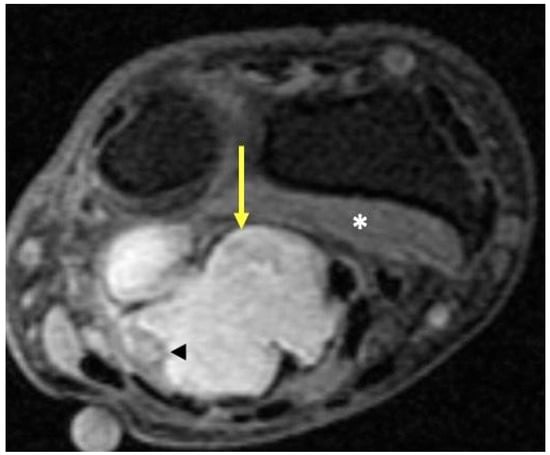

2.6. Vascular Tumors and Malformations

2.6.1. Clinical Features

2.6.2. Imaging Appearance